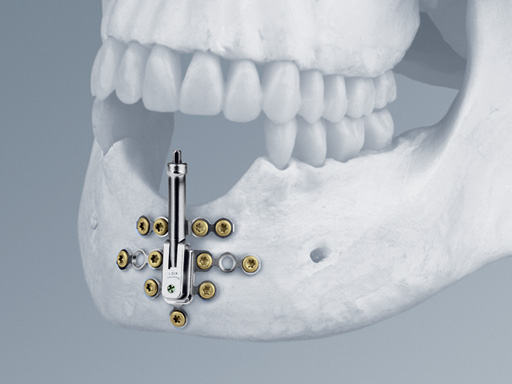

The new Alveolar Distractor is an internal distraction device intended for vertical bone augmentation of the alveolar ridge in the mandible and the maxilla with a deficit of in bony height and soft-tissue coverage.

The distraction device consists of:

• The lower body with angulation mechanism which is welded to the base plate

• The upper body with distraction mechanism consisting of a threaded rod as well as a threaded transport plate.

One of the main features of the Alveolar Distractor is its vector adjustability: an angulation mechanism allows easy intraoperative selection of the distraction vector. Therefore, extensive adaptations to the foot plates can be avoided. The distractor can be angled up to 52 toward the buccal and 32 toward the lingual side. After adjusting the vector, the angulation mechanism must be relocked by tightening the fixation screw.

The rigid base plate, with optional screw holes next to the angulation mechanism, allows safe anchorage of the distraction device in the residual bone segment. This leads to high stability ensuring rigidity and preventing potential unfavorable distraction vector changes due to soft-tissue pull.

Three different implant sizes allow for 8 mm, 12 mm, and 16 mm of distraction. This choice offers the flexibility to fit the distractor to different anatomical conditions. To achieve the desired distraction result, the two bodies are connected with a pin to change the plane angle of the bone plates in one dimension. The angulation mechanism allows for fixation of this angle. This feature allows for a single, individual intraoperative adjustment of the distraction vector and addresses the importance of a correct distraction vector in a sagittal plane.

The plate is extended vertically to improve the vertical stability of the system helping to withstand lingual and palatal soft-tissue tension and therefore also guarantees a stable distraction vector. This device has housing for the distraction body to prevent soft-tissue irritation as there is no exposure of the surrounding soft tissue to the threaded rod during distraction and latency.